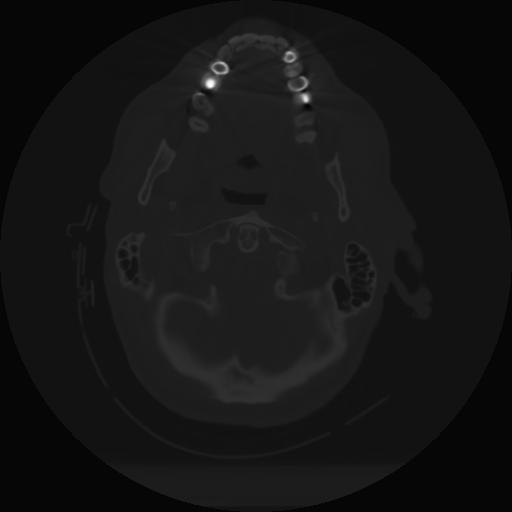

10 P.BLANDAS,,Axial,2.0,P.BLANDAS,,